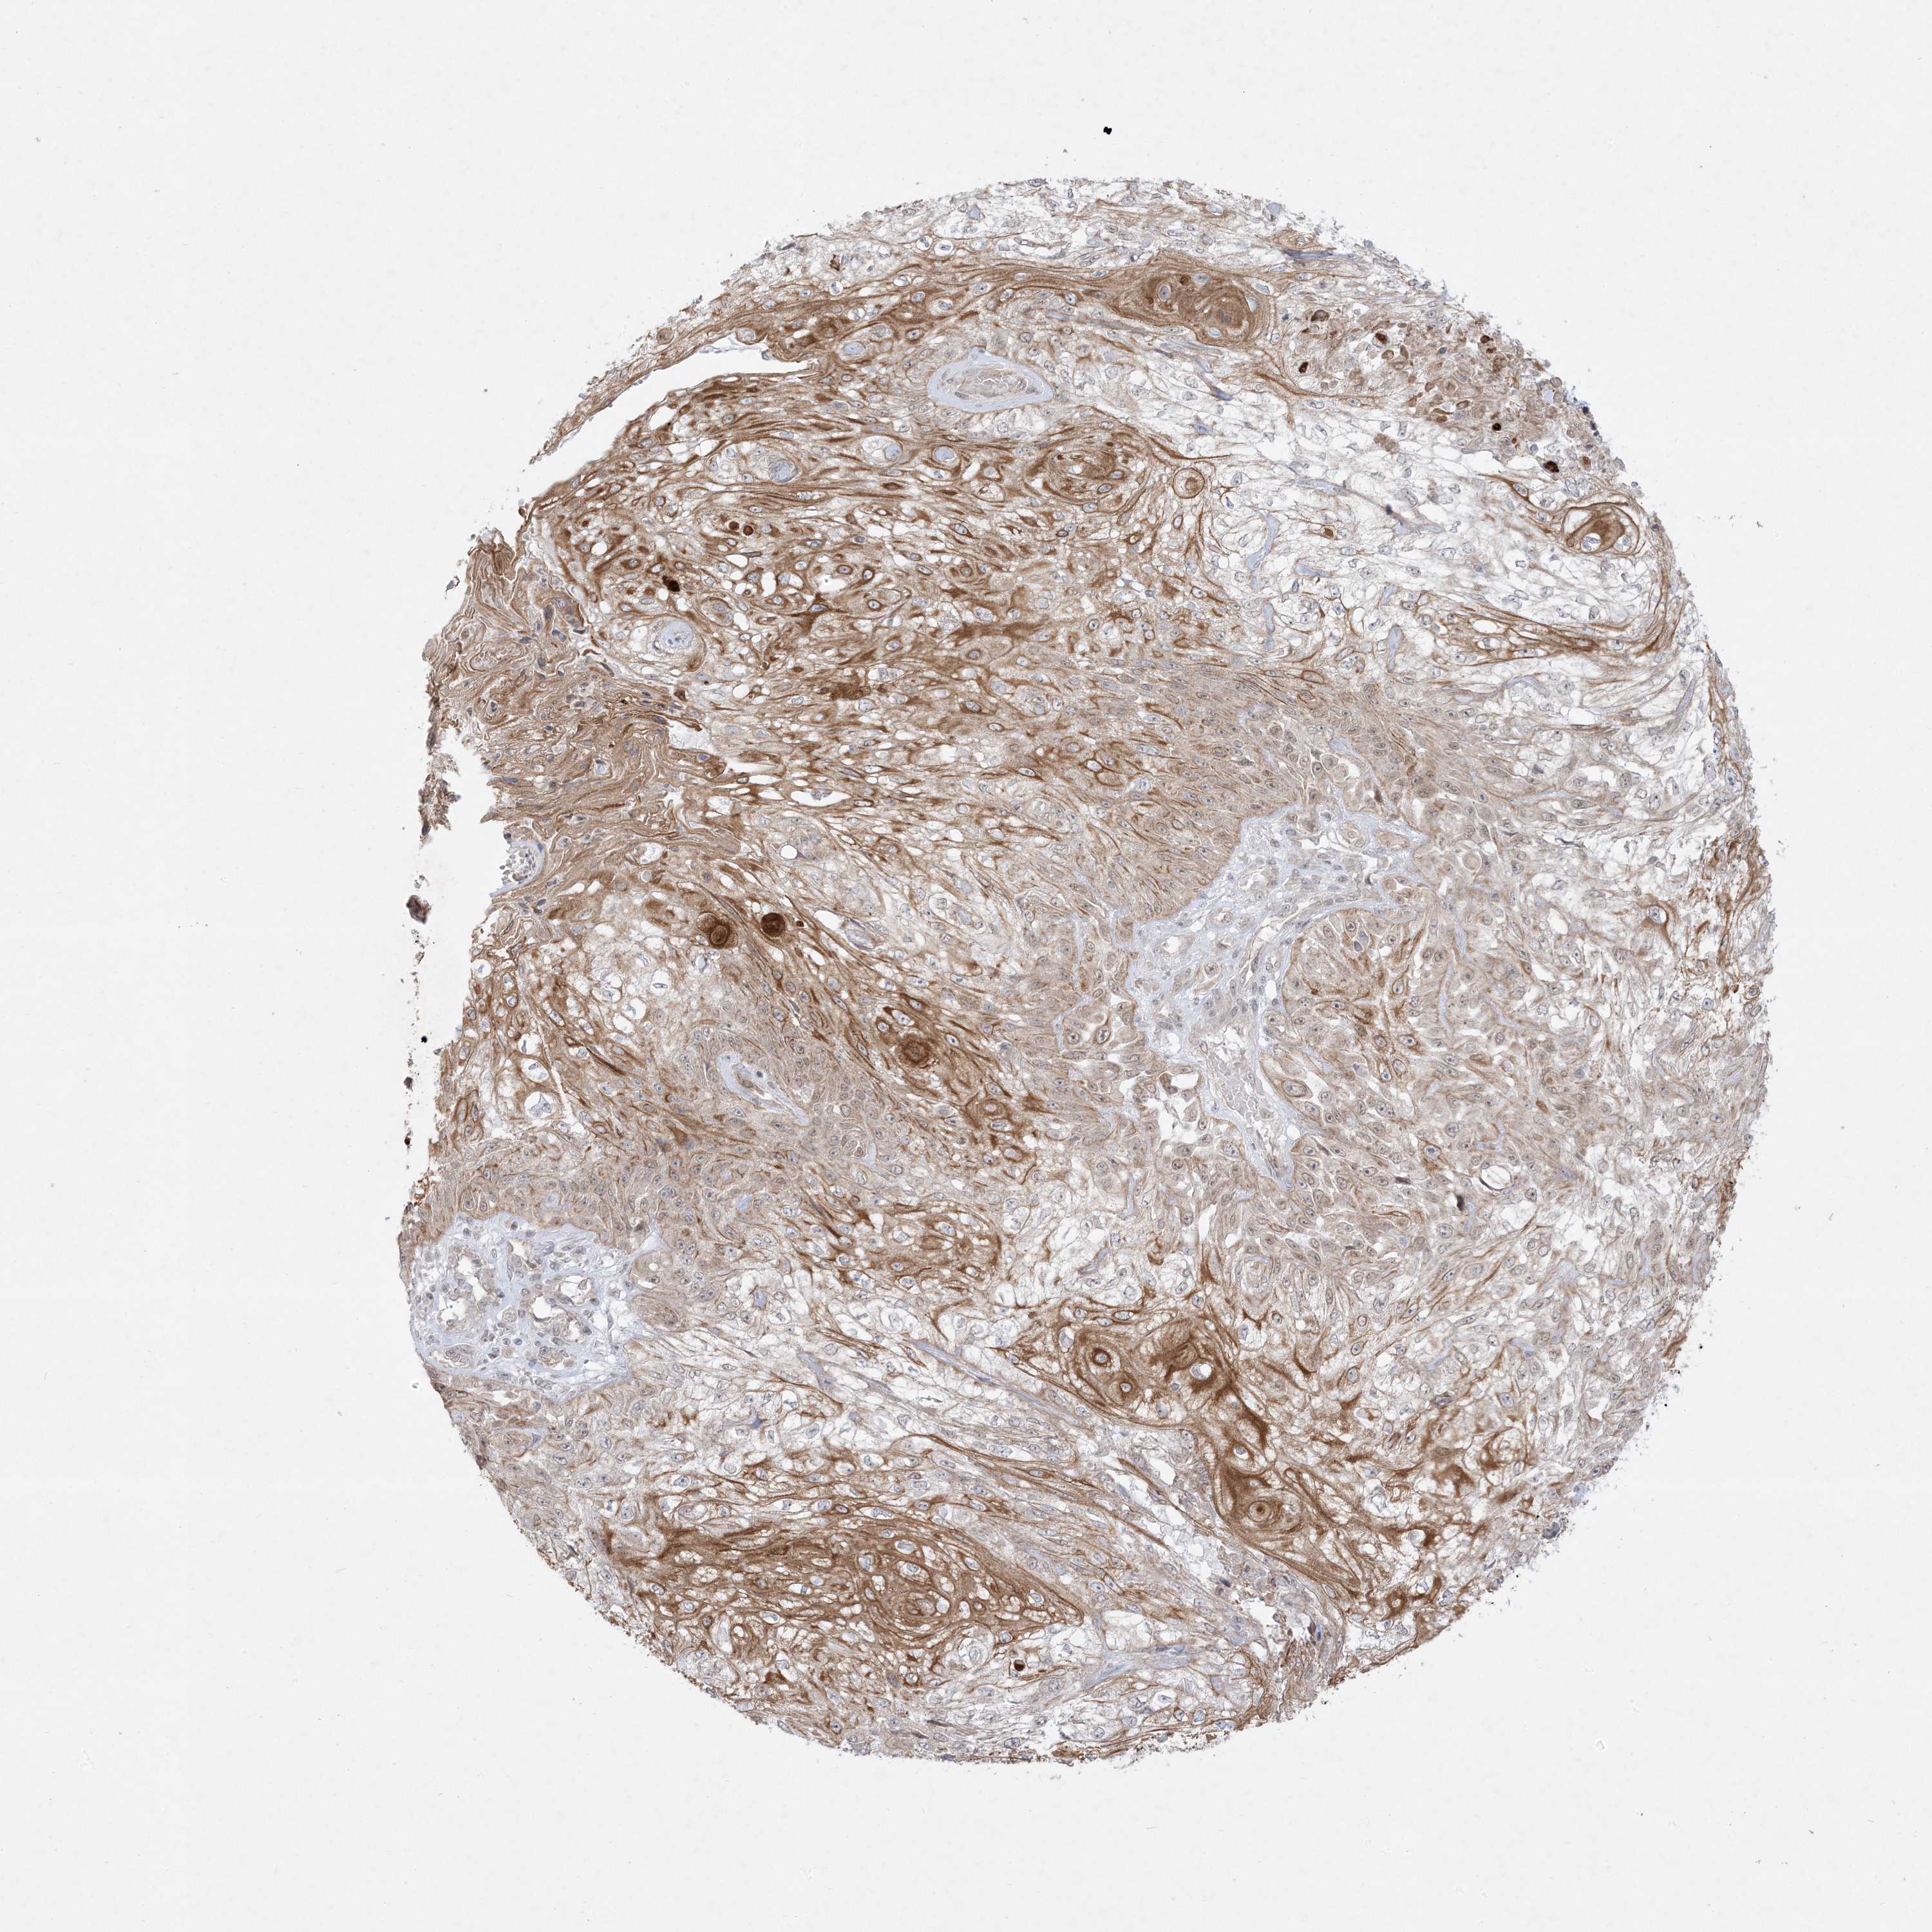

CANCER SKIN CANCER Show tissue menu

Basal cell and squamous cell cancer

SKIN CANCER - Protein expressioni

A mouse-over function shows sample information and annotation data. Click on an image to view it in a full screen mode. Samples can be filtered based on level of antibody staining by selecting one or several of the following categories: high, medium, low and not detected. The assay and annotation is described here.

Each image is clickable and will lead to virtual microscopy that enables deeper exploration of all samples and also displays staining intensity scores, fraction scores and subcellular localization as well as patient and tissue information for each sample.

Antibody HPA036070

Antibody HPA036071

Antibody CAB032952

Staining

High

Medium

Low

Not detected

Basal cell carcinoma

Squamous cell carcinoma, NOS

Squamous cell carcinoma, metastatic, NOS